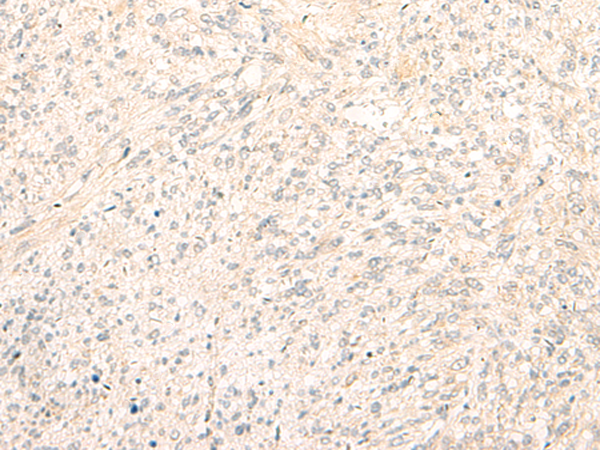

分类: 科研抗体货号: P11104别名: YC1, MSSP, SCR2, HCC-4, MSSP-1, MSSP-2, MSSP-3, C2orf12应用: IHC反应种属: Human, Mouse, Rat